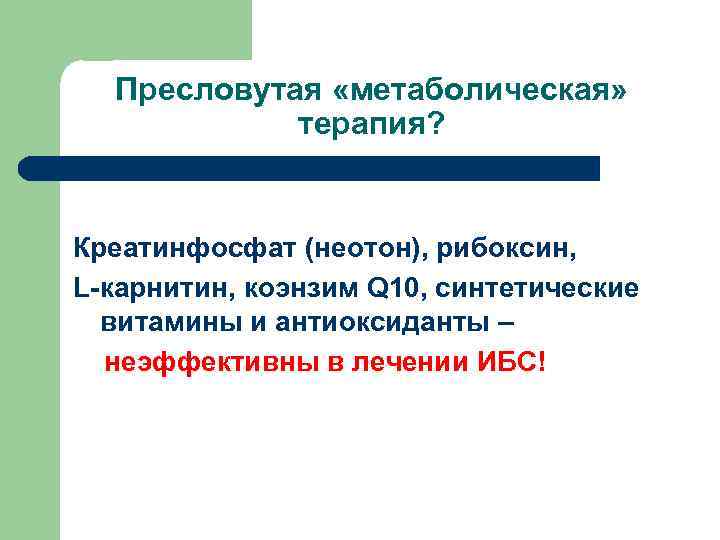

Пресловутая «метаболическая» терапия? Креатинфосфат (неотон), рибоксин, L-карнитин, коэнзим Q 10, синтетические витамины и антиоксиданты – неэффективны в лечении ИБС!